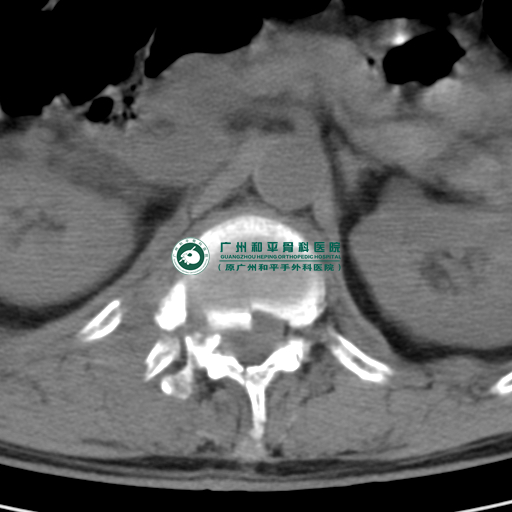

医生为他做完CT检查后发现胸椎暴裂性骨折、骨盆骨折、多发性肋骨骨折、血气胸,其间陈先生还出冷汗、四肢冰冷,胸部、腰背部、双髋部剧烈疼痛,胸闷,呼吸不畅,双下肢不能活动,已经不能回忆事情发生的经过。鉴于其伤势的严重性,在当地医院给予输液、吸氧、导尿治疗后转诊到位于广州市海珠区的广州和平骨科医院求医。

胸椎暴裂性骨折

广州和平骨科医院骨科主任、副主任医师胡铁山接诊陈先生,发现陈先生病情危重,已经出现失血性休克;多发性肋骨骨折、肺挫伤,血气胸,胸椎体暴裂性骨折并不完全性截瘫,骨盆骨折,腰椎骨折。为了及时抢救病人生命,胡铁山主任立即指挥骨科医生团队给陈先生补充液体量,配血,输血等抗休克治疗并完善相关辅助检查。由于病情危重,胡铁山主任为陈先生下病危通知并向他的家属解释清楚病情的危重性。经过抢救后陈先生失血性休克得以纠正,血压平稳,尿量正常,但他的病情危重,随时可能继续恶化,危及生命,广州和平骨科医院骨科的值班医生一直密切注意观察他病情变化,陈先生家人轮流守着,焦急的心一直悬挂着未曾放松。